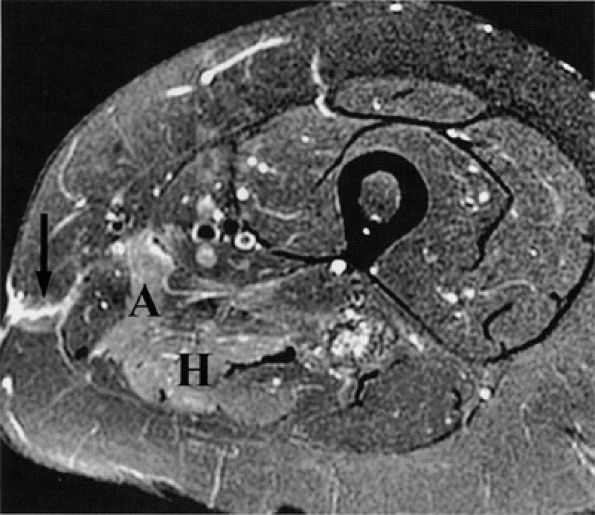

FIGURE 6.12 ● Denervation edema after resection of a sciatic nerve tumor. This axial T2-weighted image demonstrates denervation edema in the hamstring muscles (H) and adductor magnus muscle (A).

|

FIGURE 6.13 ● Lumbosacral plexopathy with denervation edema in the femoral, obturator, and sciatic nerve distribution. Increased signal in the vasti muscles (V) and adductor magnus (A) and hamstring muscles (arrow) is shown on this axial T2-weighted fat-suppressed image.